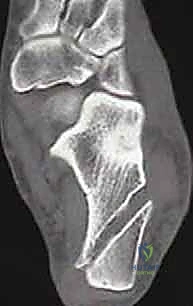

لا يكتفي الدكتور هطيف بالفحص السريري، بل يعتمد على أحدث تقنيات التصوير لتقييم حجم الضرر بدقة:

* الأشعة السينية (X-rays): لاستبعاد وجود كسور قديمة غير ملتئمة، أو وجود نتوءات عظمية، وتقييم محور القدم.

* التصوير بالرنين المغناطيسي (MRI): هو المعيار الذهبي. يوضح بدقة متناهية حالة الأربطة (تمزق جزئي، تمزق كلي، أو تندب)، ويساعد في الكشف عن أي إصابات مصاحبة مثل تمزق الأوتار الشظوية أو إصابات الغضروف المفصلي (Osteochondral Lesions).